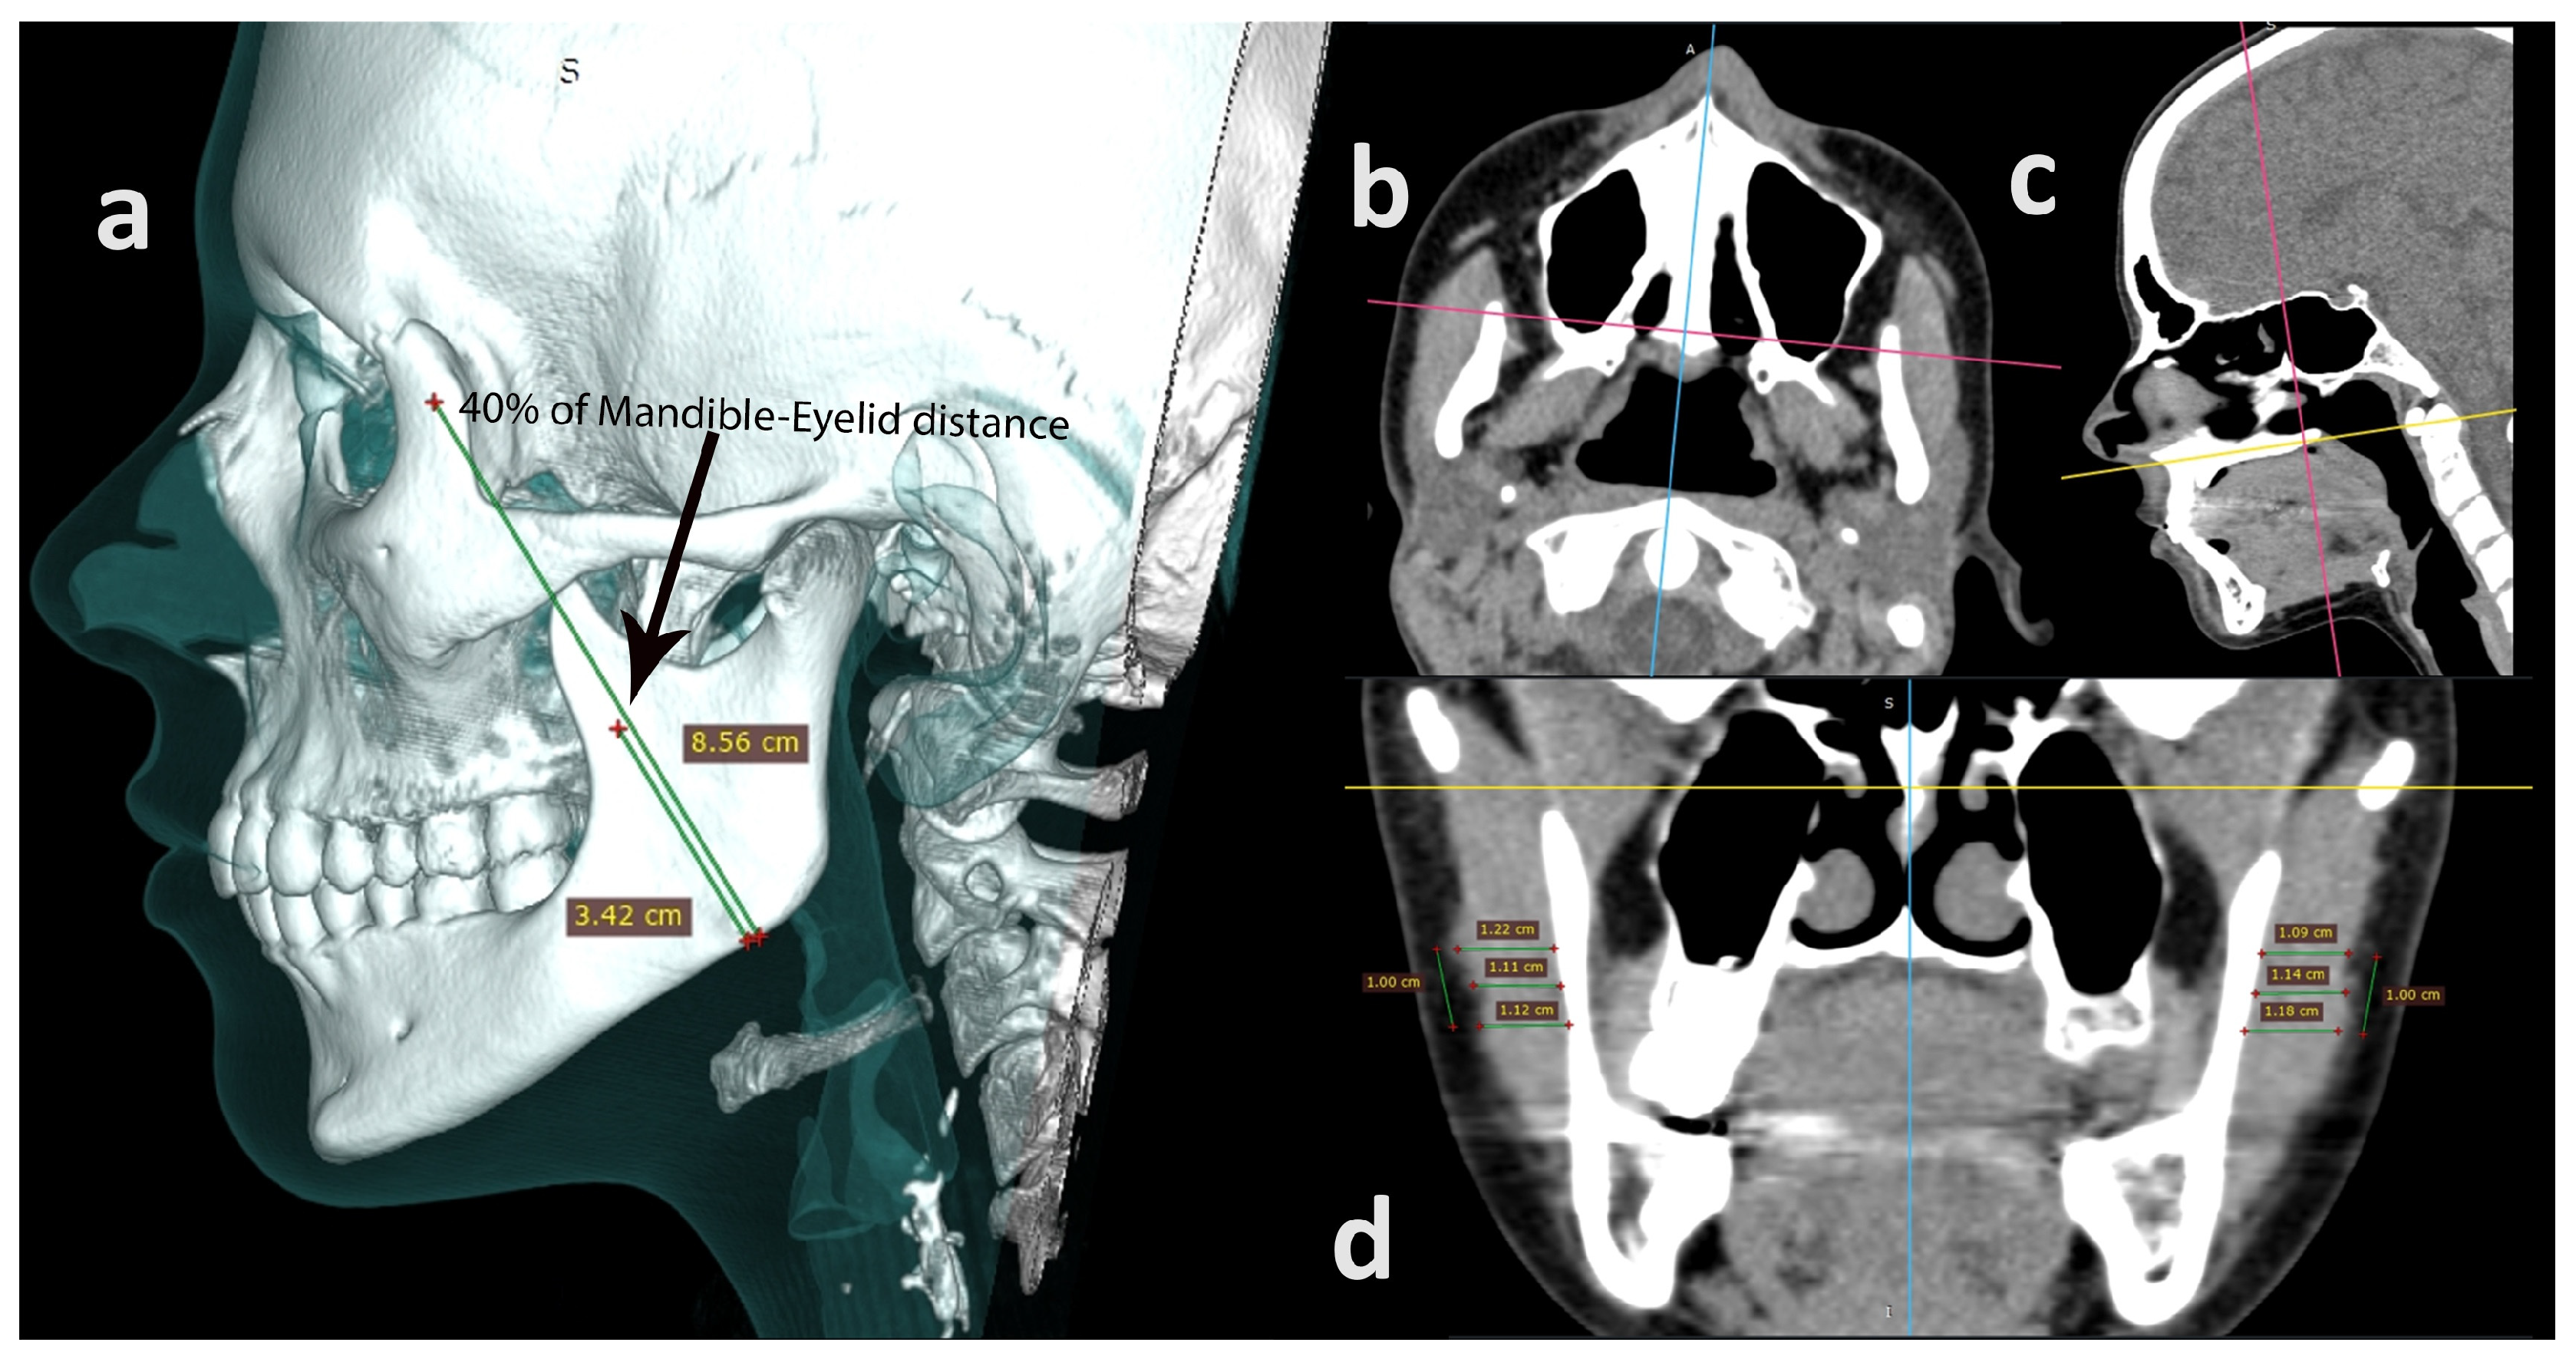

2.4. Computed Tomography

2.5.2. Computed Tomography